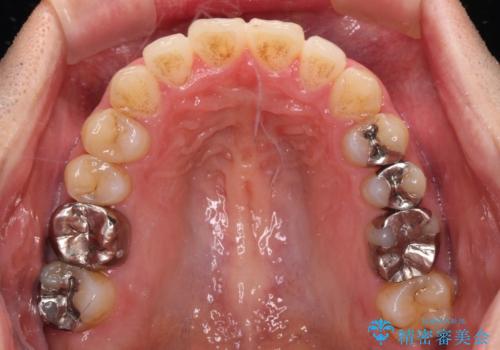

- 前歯のデコボコと、上顎前歯の突出感を気にして来院された患者様です。

通常の咬み合わせ位置と比較して、上顎の歯列が全体的に前方にある状態で、上下前歯の前後方向の位置に著しい差がありました。

奥歯には目立つ銀歯が多くあるので、矯正治療後には下顎の銀歯をセラミッククラウンやセラミックインレーにより、補綴・修復治療することとしました。